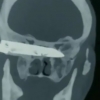

[여기는 중국] 26년간 머리에 칼날 통째로 박힌 채 살아온 남성

2020-04-14 나우뉴스 -